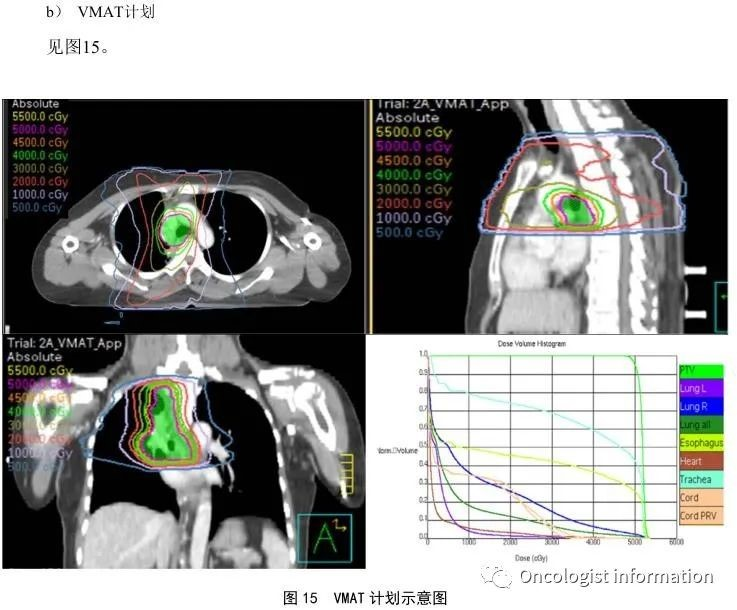

3、容积调强拉弧治疗(VMAT)

这种技术可以通过一个弧或多个弧的机架旋转来实现调强适形放射治疗,使放射剂量更加均匀地照射到肿瘤上,减少了放疗时间和对周围正常组织的损伤。它是一种将旋转治疗的剂量学优势与调强放疗的剂量雕刻能力相结合的放疗方式,通过连续旋转治疗为获得理想剂量分布提供了极大灵活性。这种技术在治疗颅内单发或多发脑转移大分割放疗的患者时效果尤为显著,同时也适用于治疗较小或复杂的肺部病灶。